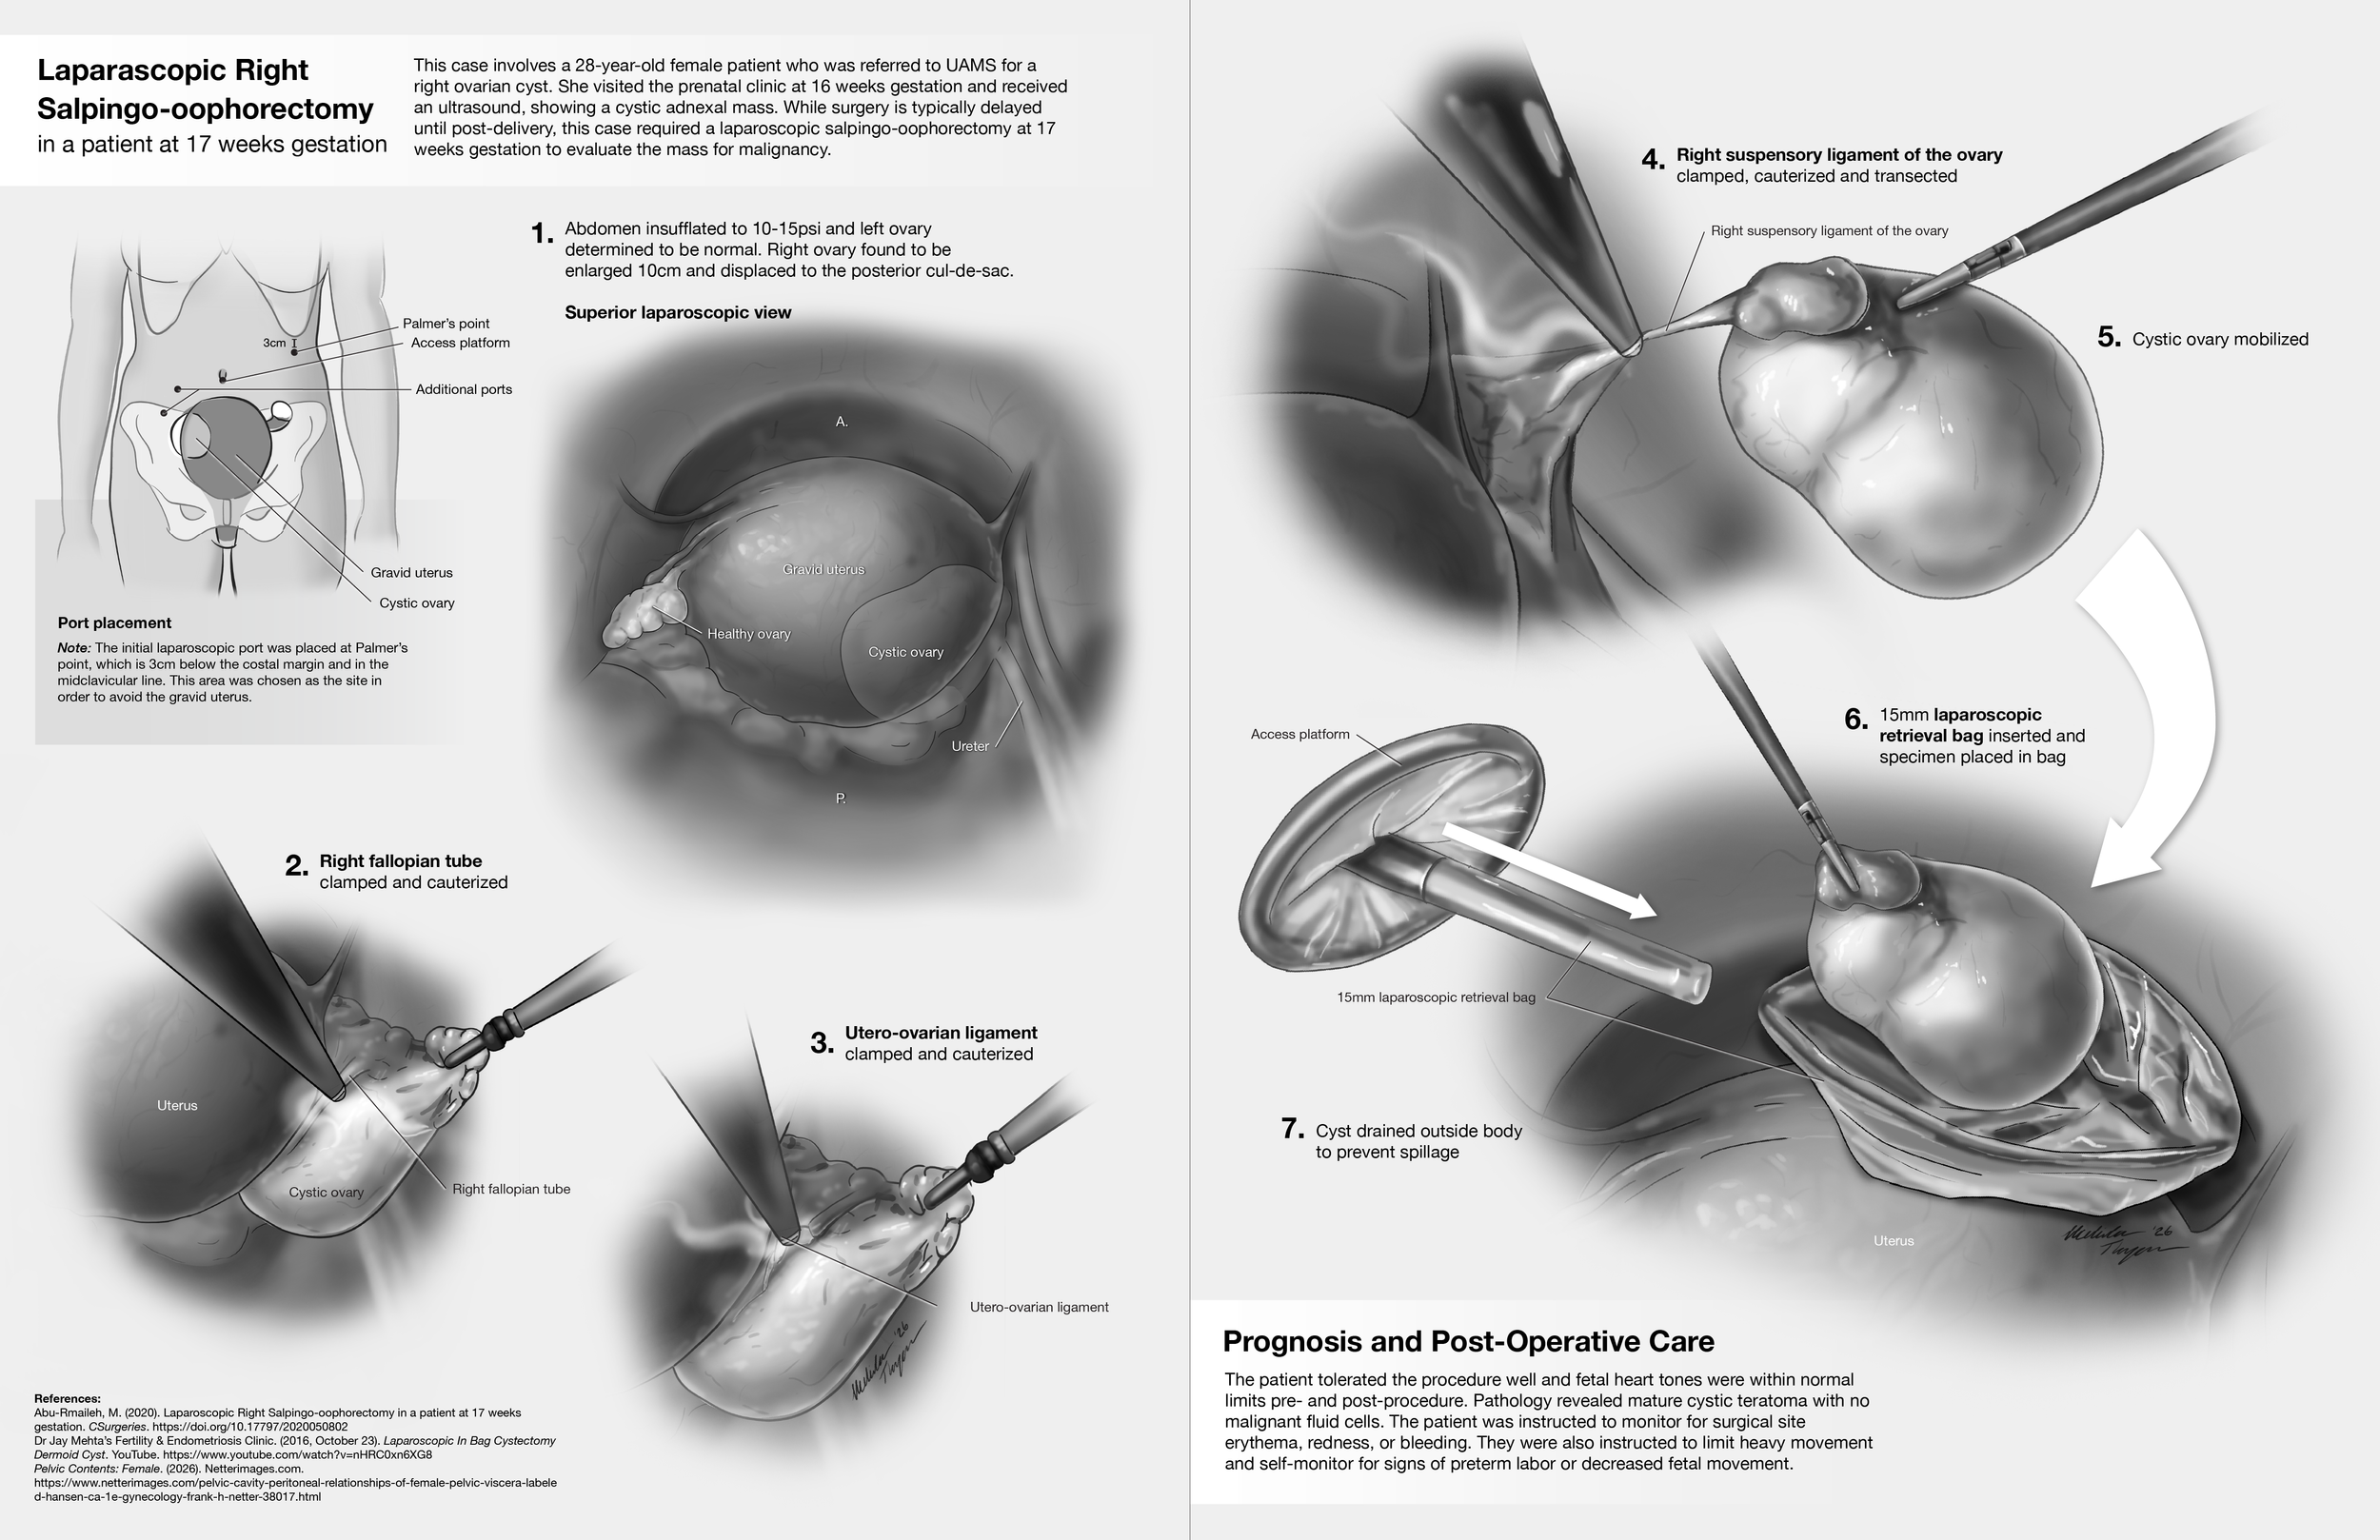

Academic Surgical Illustration: Laparascopic right salpingo-oophrectomy in a patient at 17 weeks gestation